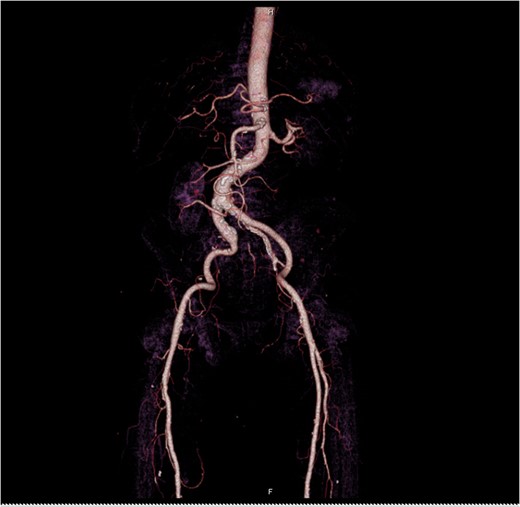

At Emergency department, physical exam showed hypotension blood pressure 70/50 mmHg and per rectal exam showed blood clot with enlarged prostate. After resuscitation until stable vital sign, he was sent for colonoscopy but cannot be evaluated due to a lot of blood clots in the rectum. He was admitted for observation and we planned to repeat colonoscopy again following day because he was stable and bleeding was stopped. Following day after admitting, he had massive lower gastrointestinal bleeding again fresh blood ~1000 ml from his anus. His blood pressure was lower 80/50 mmHg. After stabilization, we planned to send the patient to angiogram for embolization. But the patient had a problem vascular access site and then send to computed tomography angiography (CTA) for evaluate access site. We found 3 cm aneurysm of right internal iliac artery with partial thrombus and attached to rectosigmoid colon with leakage of contrast into sigmoid lumen (Figs 1–2). He was sent to operating room during transferring we gave blood transfusion and then emergency explore laparotomy was performed, the operation performed by partial aneurysmectomy, ligated right internal iliac, wedge resection rectum wall and temporary abdominal closure with swab packing due to bowel distension and abdominal pressure was high. The operative time was around 3 hours and blood loss 6000 cc. He was sent to operating room for change swab packing on Day 3 and permanent abdominal closure on Day 5. During postoperative period, he developed acute cholecystitis and underwent open cholecystectomy. After admit for 1 month, he was discharged with fully recovery.

Axial view iliac aneurysm with partially thrombose contact rectosigmoid colon and contrast leak.